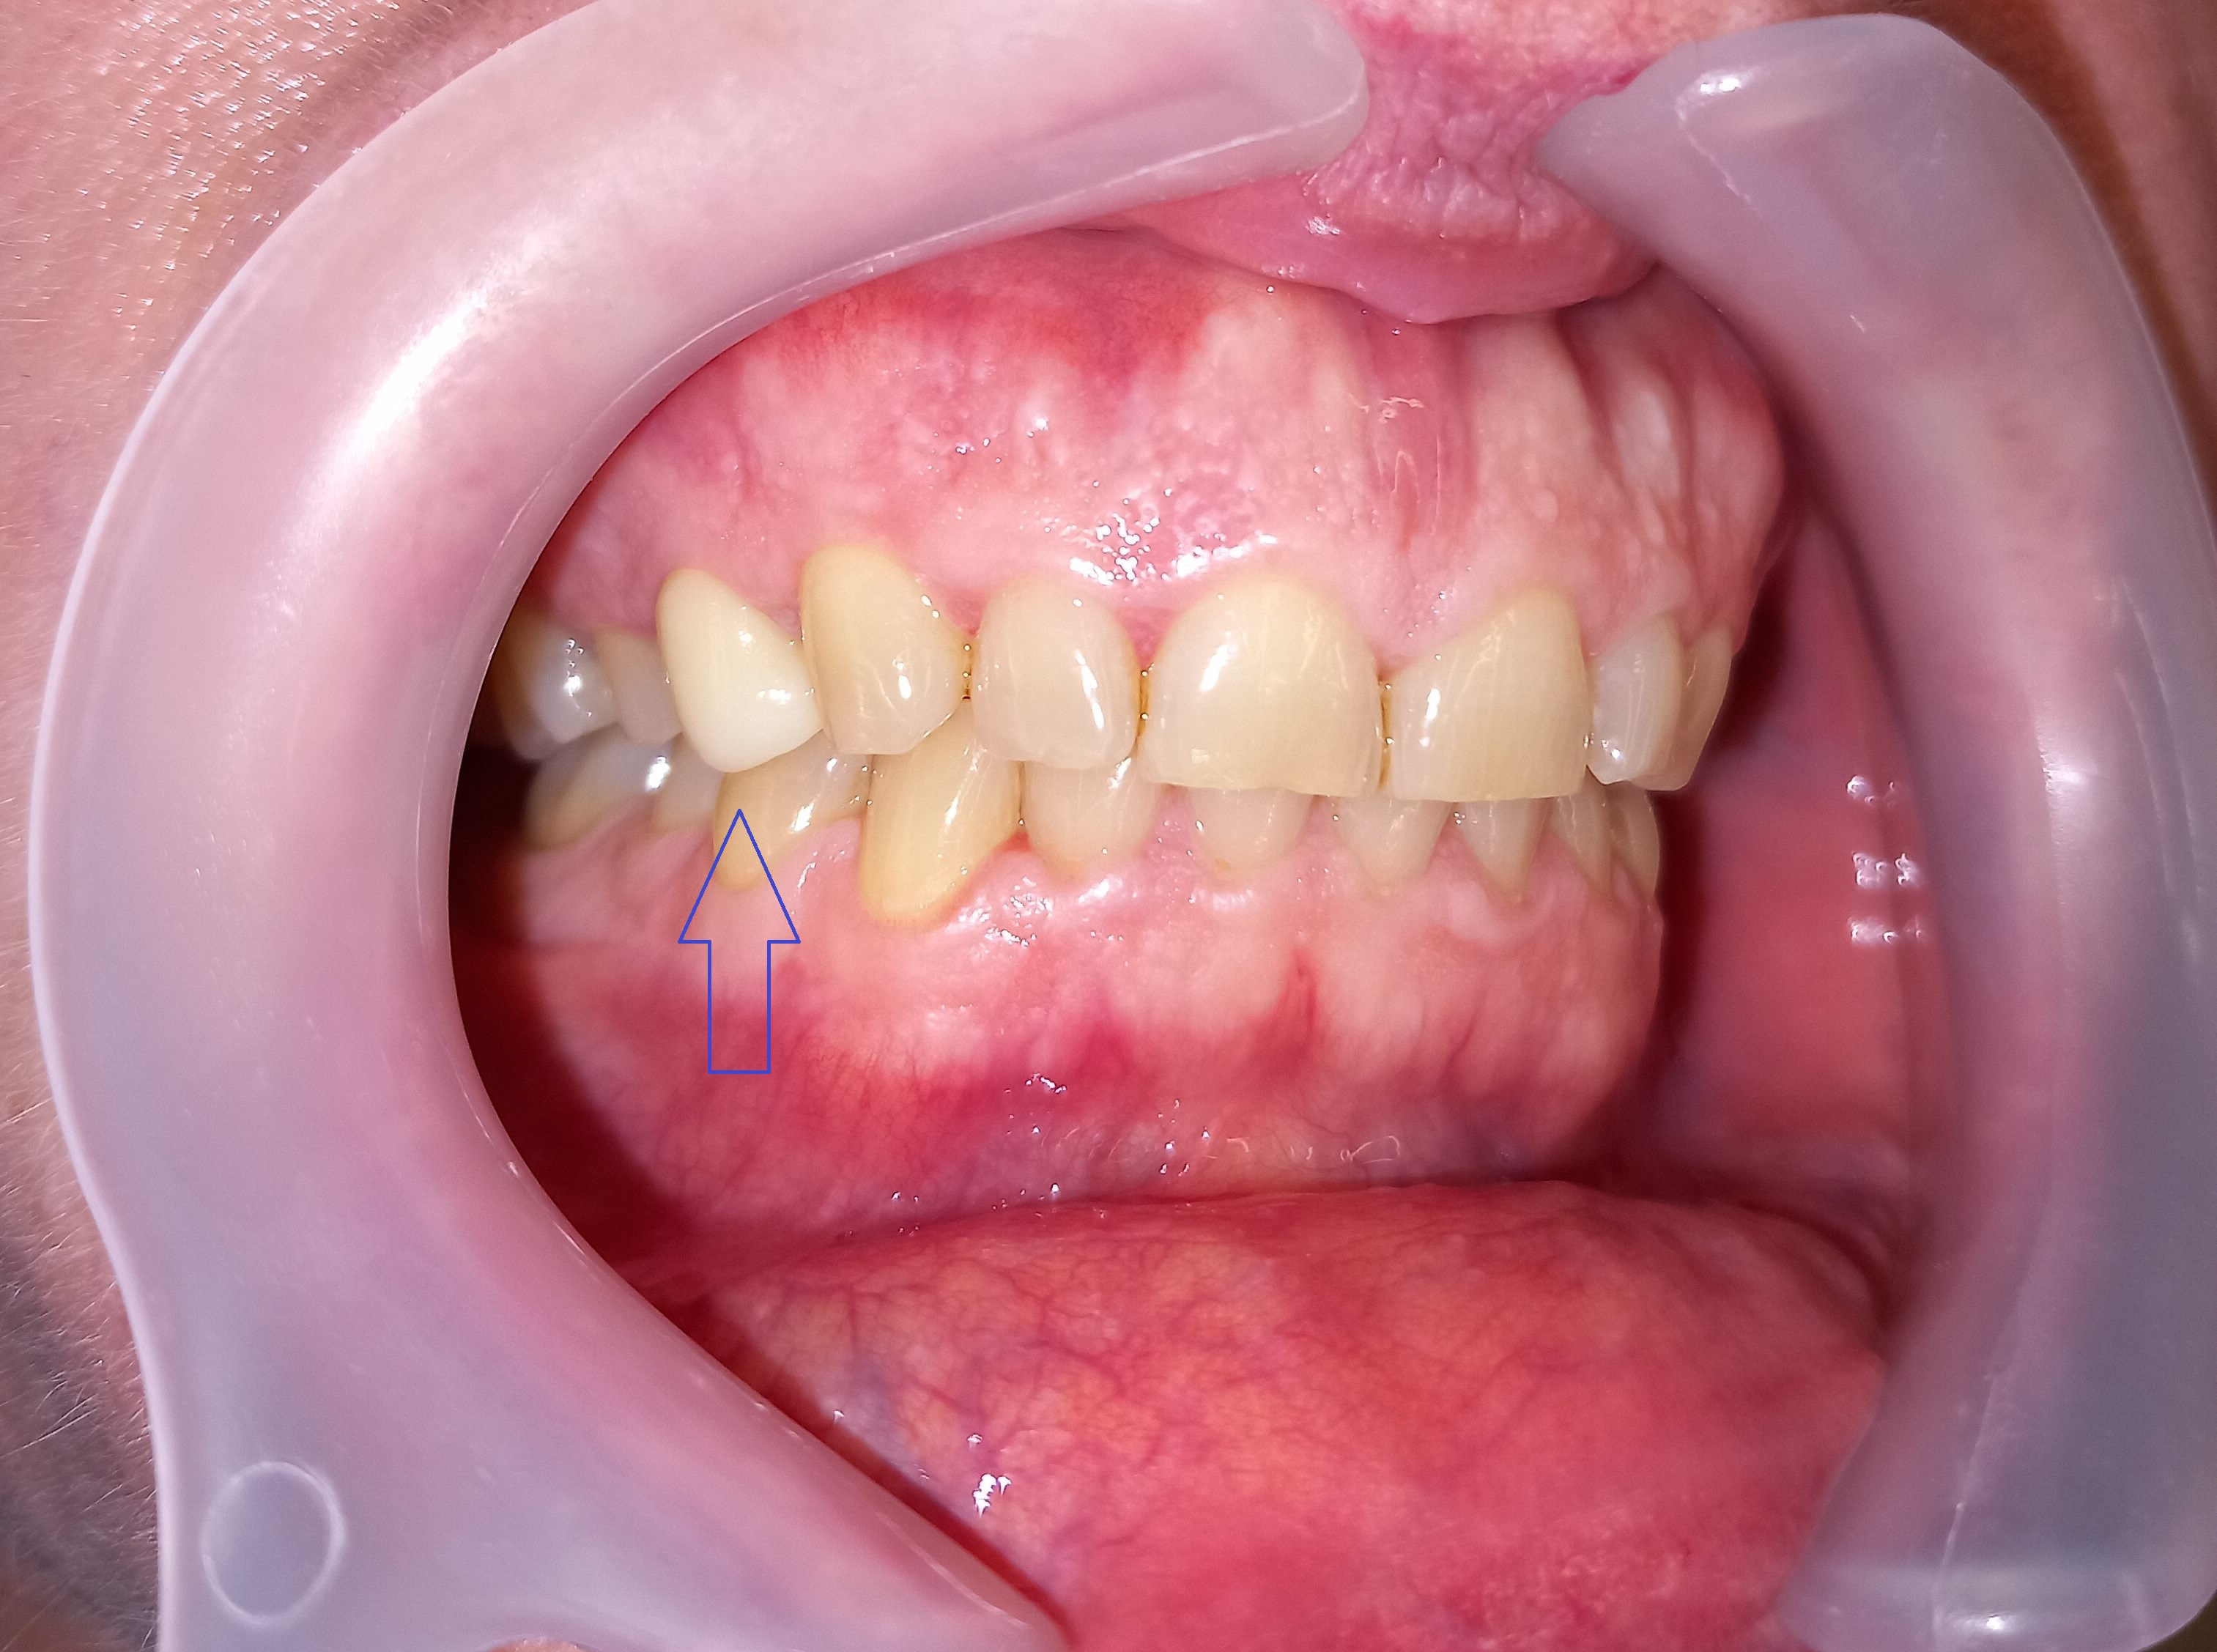

Η ασθενής επιθυμούσε οπωσδήποτε να διορθώσει το χαμόγελό της, το οποίο χρόνια την δυσαρεστούσε καθώς το ένα δόντι ήταν στραβό και το άλλο πολύ μικρό. Αποφάσιστηκε η διόρθωση του χαμόγελου με ολοκεραμικές θήκες ζιρκονίου. Το τελικό αποτέλεσμα είναι εκπληκτικό, καθώς η ασθενής επιθυμούσε οι θήκες της να μην ξεχωρίζουν καθόλου από τα φυσικά της δόντια όταν γελά, γεγονός που επιβεβαιώθηκε. Μετά τη σωστή χρωματοληψία και την άρτια συνεργασία με τον οδοντοτεχνίτη η ασθενής έχει μία νέα προσθετική δουλειά στο στόμα της που είναι πολύ όμορφη αισθητικά.

ΠΡΙΝ

ΜΕΤΑ